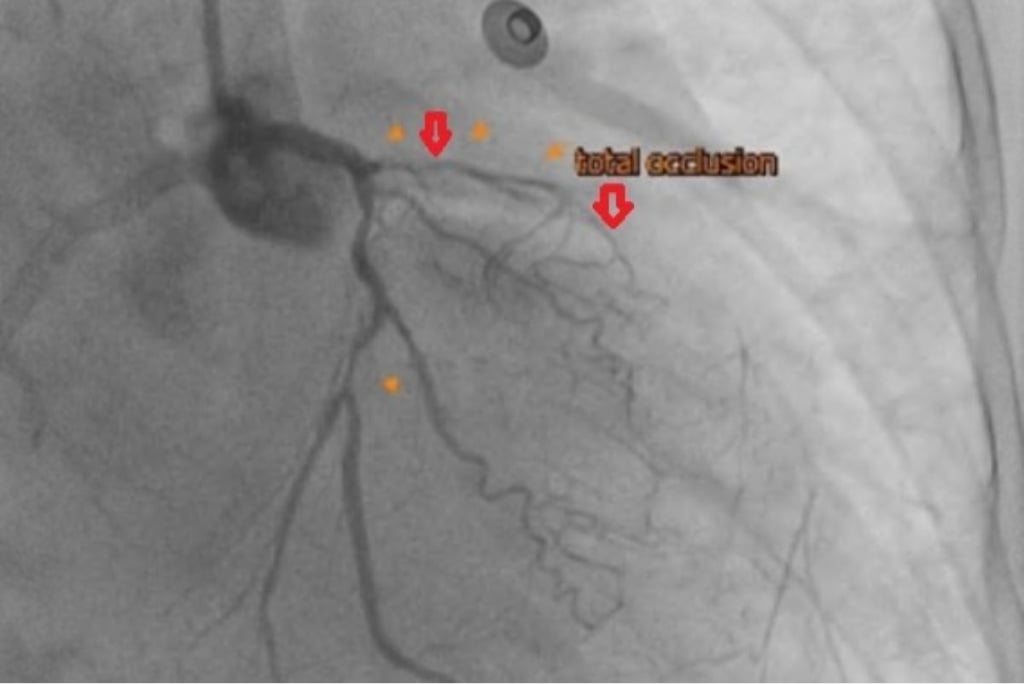

63歲的陳奶奶長年患有三高,三個月前出現呼吸越來越喘、胸悶不適等症狀,來到台北慈濟醫院心臟血管科就診並收治入院。心導管檢查發現其左前降支合併完全阻塞左迴旋枝狹窄,心臟超音波發現左心室收縮功能不到30%(正常為50-60%),診斷為缺血性心肌病變,即冠狀動脈阻塞導致的慢性心臟衰竭,因此照會心臟血管外科楊凱文醫師。

63歲的陳奶奶長年患有三高,三個月前出現呼吸越來越喘、胸悶不適等症狀,經心導管檢查發現其左前降支合併完全阻塞左迴旋枝狹窄,心臟超音波發現左心室收縮功能不到30%(正常為50-60%),診斷為缺血性心肌病變,即冠狀動脈阻塞導致的慢性心臟衰竭,因此照會心臟血管外科楊凱文醫師。

後續透過心臟核磁共振,醫師楊凱文評估病人仍有可挽救的心肌,經過心臟內外科跨團隊和患者充分討論後,決定採取複合式冠脈血流重建的治療策略。由醫師楊凱文執行達文西微創冠狀動脈繞道手術,以左內乳動脈為繞道血管,重新供應左前降支的血流,後續是需要再由心臟血管科醫師進行心導管疏通左迴旋枝的狹窄。術後病患左心室收縮功能明顯進步,目前於門診定期回診追蹤。

冠狀動脈疾病的診斷需結合多項檢查綜合評估,除了透過心導管檢查確認血管狹窄位置與嚴重程度,也會輔以心電圖與心臟超音波了解心臟節律與收縮功能是否存在異常。在心臟收縮功能較差的病患,則可能藉由核磁共振評估是否還有可挽救的心肌存在。在治療選擇上有心導管支架置放及外科手術,前者適用於單一血管狹窄且情況不嚴重或病人手術風險過高;後者則有傳統開胸及達文西微創手術兩種,適用於多條血管嚴重狹窄甚至阻塞的情形。